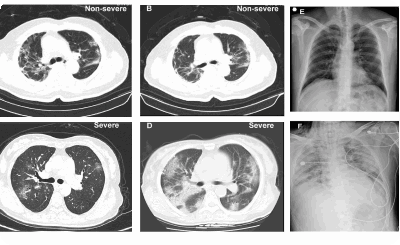

В 2020 году была разработана эмпирическая шкала визуальной оценки легких, в которой КТ-0, КТ-1, КТ-2, КТ-3 и КТ-4 соответствуют стадии заболевания и, соответственно, степени поражения легких.

Врач изучает каждую долю легкого (всего 5) на посрезовых сканах в поперечной и фронтальных плоскостях и оценивает объем поражения каждой по пятибалльной шкале. Если признаки воспаления отсутствуют, рентгенолог присваивает значение 0 и так далее. Если воспалительные очаги и инфильтраты присутствуют в нескольких сегментах, такую пневмонию называют полисегментарной. При коронавирусе пациентам чаще всего диагностируют двустороннюю полисегментарную пневмонию. При своевременном обращении за медицинской помощью распространение инфекции в легких можно остановить.

Степени поражения легких при коронавирусе на КТ

В заключении КТ легких пациенты видят аббревиатуры: КТ-0, КТ-1, КТ-2, КТ-3 и КТ-4 Что они обозначают?

- КТ-0 —очаги воспаления и инфильтраты не выявлены, легкие «чистые»;

- КТ-1 —поражение легких до 25%;

- КТ-2 —поражение легких 25-50%;

- КТ-3 —поражение легких 50-75%;

- КТ-4 —поражение легких > 75%.

По данным исследования «Time Course of Lung Changes at Chest CT during Recovery from Coronavirus Disease 2019 (COVID-19)», опубликованного в июле 2020 года в международном журнале Radiology, максимальное поражение легких (пик пневмонии) у большинства пациентов наблюдается на 10 день заболевания. В выборку не вошли пациенты со специфическими осложнениями, такими как ОРДС, кардиогенный отек легкого, тромбоз, тяжелые последствия которых носят непредсказуемый характер.